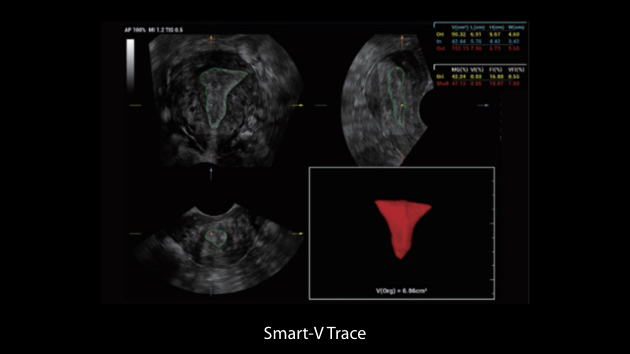

Nuewa I9 Elite Edition ├© progettato appositamente per l'assistenza sanitaria a donne e neonati e offre un'esperienza innovativa sviluppata sulla base di conoscenze approfondite relative a scenari clinici complessi, per risposte accurate e tempestive, nonch├® un'efficienza e un'esperienza utente eccezionali